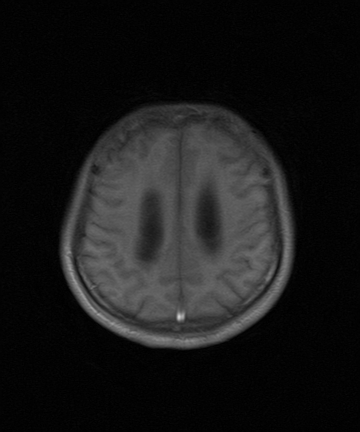

考虑第四脑室室管膜瘤并梗阻性脑积水;部分性空蝶鞍;左侧上颌窦粘膜下囊肿。

考虑第四脑室室管膜瘤【血供丰富血管母细胞瘤可能】并梗阻性脑积水;部分性空蝶鞍;左侧上颌窦粘膜下囊肿。